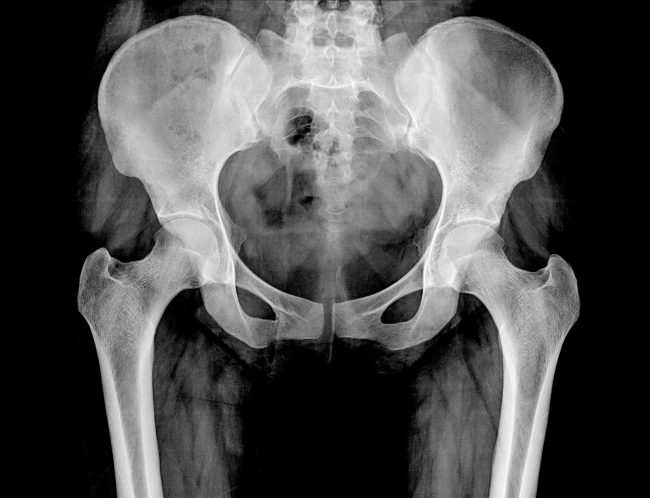

De lies als bron van sportblessures en hoe de osteopaat kan helpen

Liesklachten zijn heel vervelend. Ze hinderen ons tijdens het sporten of recreatief wandelen. Maar ook in het dagelijks leven zijn ze storend. Als partner van de heup is de lies een scharnierpunt in ons lichaam. Het hoeft dan ook niet te verbazen dat heel wat klachten die elders opduiken vertrekken vanuit de lies. De lies…